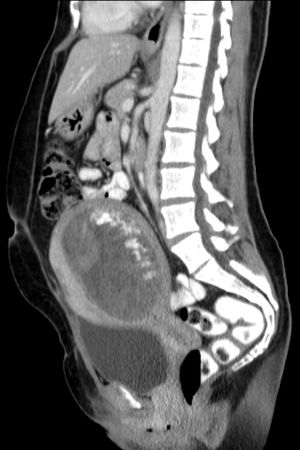

초음파 사진에서 기태는 포도송이("포도송이 떼", "벌집 자궁", "눈보라")와 유사하게 나타난다.[14] CT 촬영을 통해 자궁강 내에 과립상의 구조가 관찰된다.